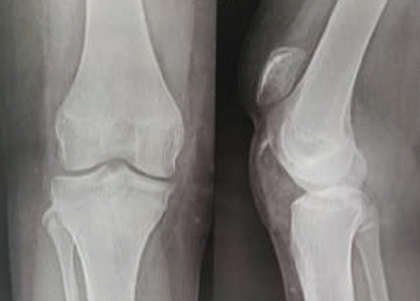

Medial Hoffa’s Fracture Treated with Subvastus Approach – Case Series

Parimal Vairagade , Akhilesh Khobragade , Devashis Barick , Kunal Parmar , Darshan Sharma , Shrikrishna Rakhunde ………………………………p.141-145